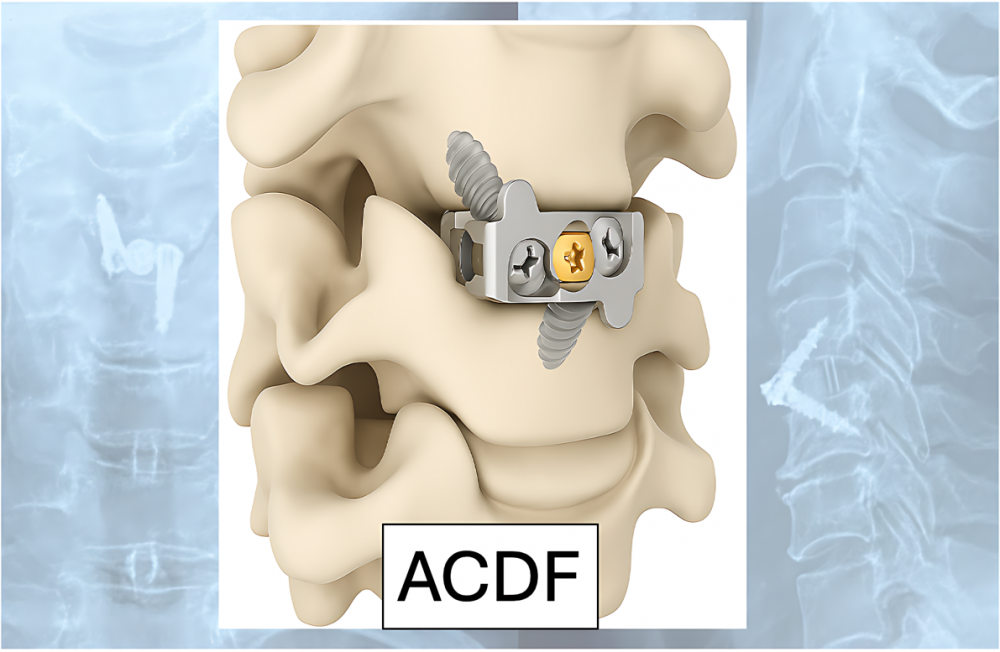

Hình 1. Phẫu thuật lấy nhân đêm và cố định cột sống cổ lối trước (ACDF – Anterior Cervical Discectomy and Fusion).

- Giai đoạn nặng hoặc thất bại điều trị nội khoa: cân nhắc phẫu thuật lấy nhân đệm và cố định cột sống cổ lối trước (ACDF – Anterior Cervical Discectomy and Fusion).